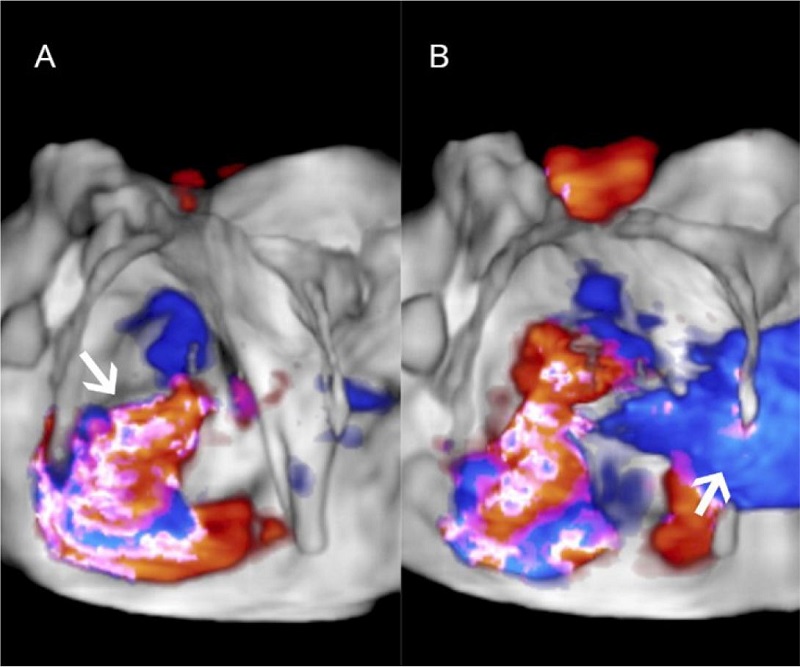

Presence of ostium secundum ASD of 14 mm with left to right shunt (Figure 2). Normal biventricular ejection fraction, enlargement of right cardiac chambers and left atrium, and noticeable MV insufficiency (Figures 3C, 4A, 4B).

MV features included annular dilation, leaflet redundancy, with failure of coaptation between A2-A3 and P2-P3, associated with multisegmental prolapsing/billowing MV components, and thickened, elongated chordae tendineae, typical of Barlow’s disease (BD) (Figures 3A, 3B, 5).